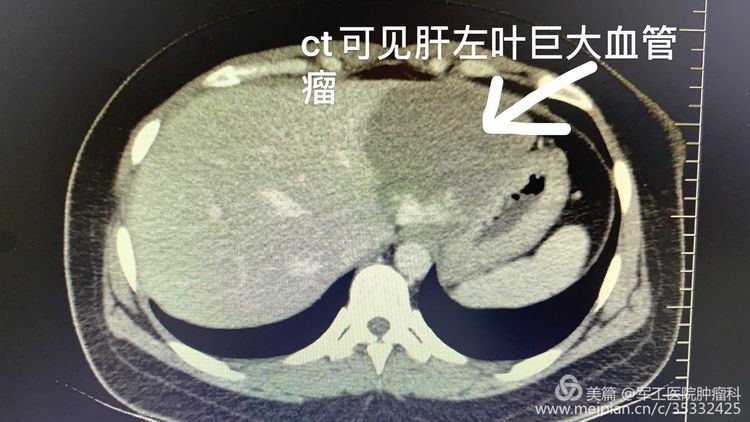

近日军工医院肿瘤科成功开展肝动脉栓塞治疗肝血管瘤患者。患者张某,31岁,因气短1年在我院呼吸科住院治疗,行影像学检查发现患者左肝外叶巨大血管瘤,最多面积约9.0cm*5.5cm,出现周围组织压迫症状,经肿瘤科白利君主任会诊建议患者行肝动脉栓塞术。术中成功将患者肝血管瘤供血血管栓塞,血管瘤逐渐萎缩。